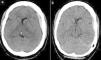

ConclusionsThere are two main mechanisms for the spontaneous resolution of acute subdural haematomas: dilution in subarachnoid space and redistribution of the haematoma in the subdural space. The primary radiological characteristic of these lesions is a hypodense rim on the outer surface of the clot. Spontaneous resolution of TASDH is unusual. Clinical and radiological surveillance is essential for appropriate management of these patients.

ConclusionesExisten 2 mecanismos principales para la resolución espontánea de hematomas subdurales agudos: la dilución en el espacio subaracnoideo y la redistribución del hematoma en el espacio subdural. La principal característica radiológica de estas lesiones es una cerco hipodenso en la superficie exterior del coágulo. La resolución espontánea de HSDAT es rara. La vigilancia clínica y radiológica es esencial para el manejo adecuado de estos pacientes.